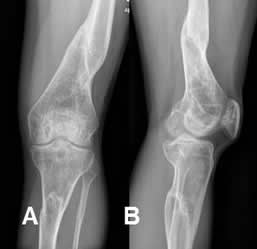

Fig 130 B. Consolidación defectuosa.

A: Rx AP. Fractura consolidada y cabalgada del fémur distal.

B: Rx lateral. Adicionalmente se aprecia rotación en el eje longitudinal de los cóndilos femorales, en relación con los platillos tibiales.